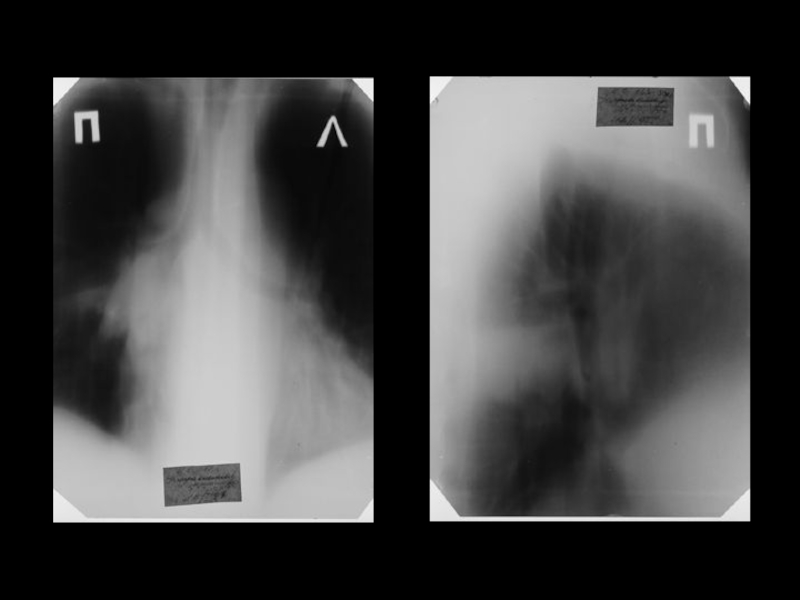

Центральный рак легкого

ЛУЧЕВАЯ ДИАГНОСТИКА РАКА ЛЕГКОГО